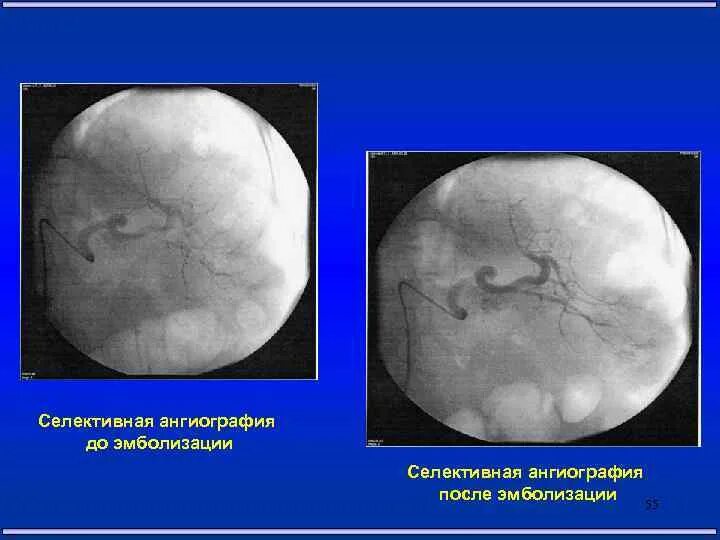

Эмболизация гемангиомы